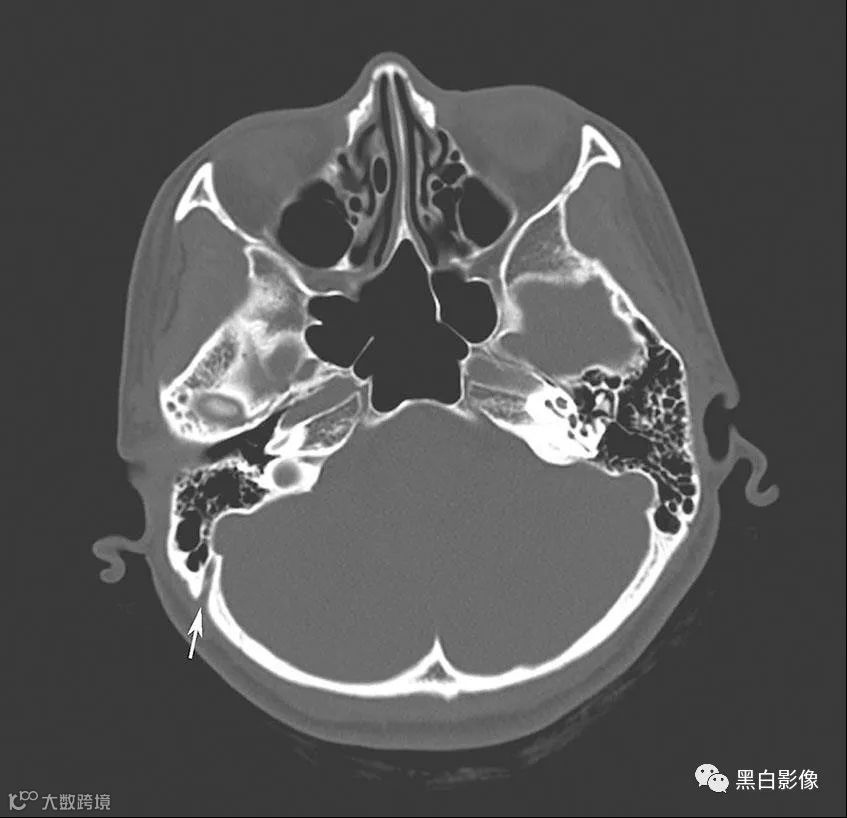

图13-2-6 导静脉的CT平扫骨窗

右侧颞骨乳突气房后方条带状低密度影(箭),考虑为乳突导静脉